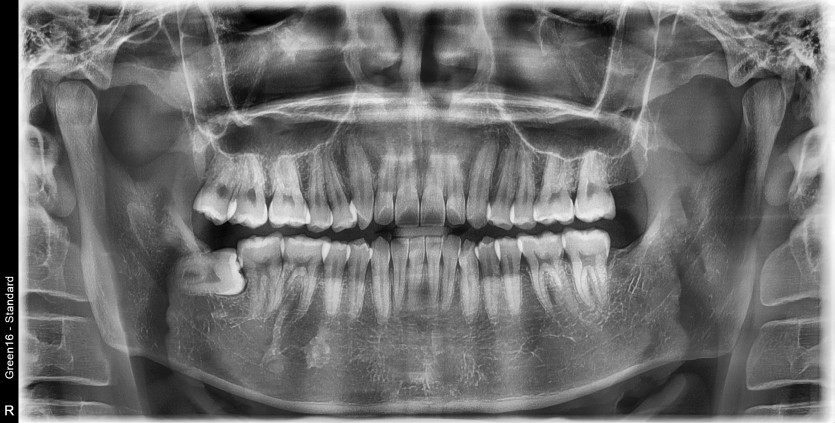

#18,48 사랑니 발치

구강 외과 전문의가 당일 발치했습니다.